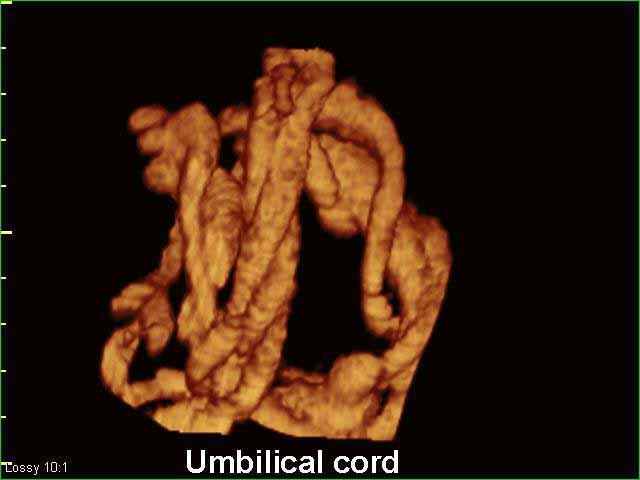

- دم الحبل السري

صور لأعضاء الجنين بجهاز الموجات فوق صوتية ثلاثي الأبعاد | الدكتور نجيب ليوس